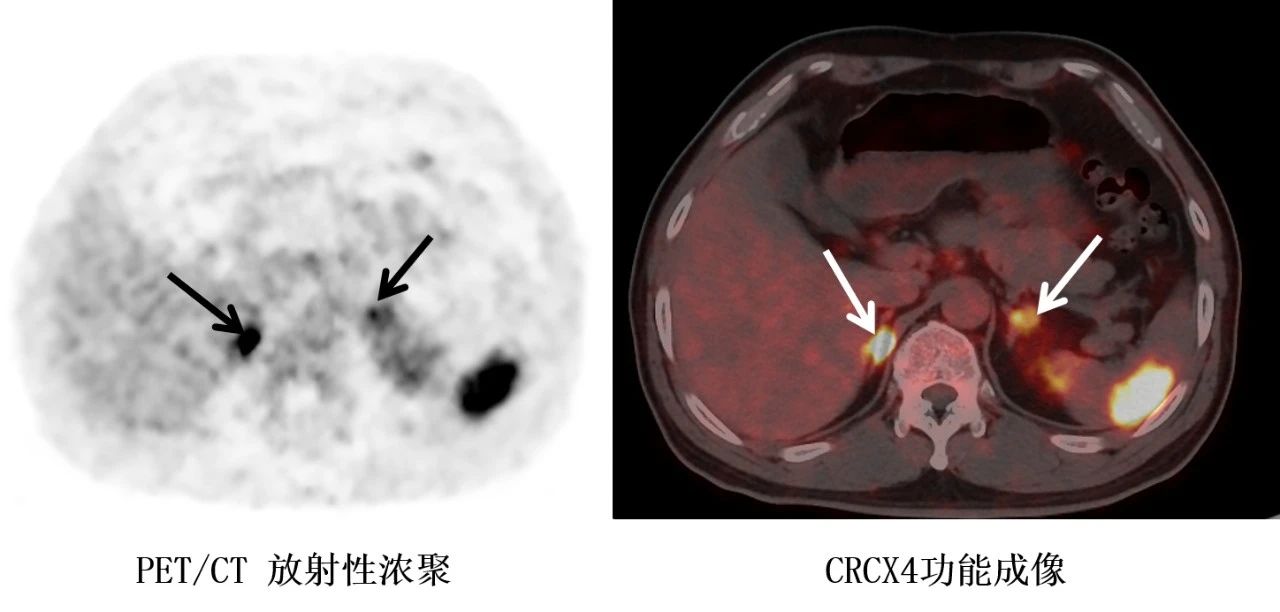

得益于内分泌与代谢病医学中心MDT团队的综合优势,在内分泌科、超声科、泌尿外科、核医学科的多学科诊疗下,通过血清电解质水平、激素检测、术前CT等手段,很快患者就确诊为原发性醛固酮增多症,为治疗争取宝贵时间。随后,利用超声造影(CEUS)、CXCR4受体显像、PET/CT核医学功能成像这三大“侦探”技术,成功对肾上腺肿瘤进一步精准定位。